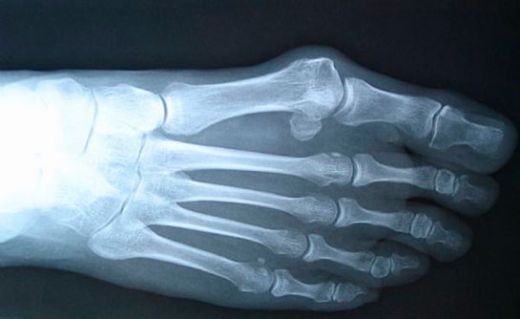

Kemik iltihabı, tıbbi literatürde osteoit olarak adlandırılan, kemik dokusunun iltihaplanması durumudur. Bu durum genellikle enfeksiyon, travma veya bağışıklık sistemi ile ilgili bozukluklar sonucu meydana gelir. Kemik iltihabının belirtileri, tedavi yöntemleri ve hastalığın seyrine dair ayrıntılı bilgi sunulacaktır.

Kemik İltihabının Belirtileri

Kemik iltihabı, çeşitli belirtilerle kendini gösterebilir. Bu belirtiler arasında:

• Ağrı: İltihaplı bölgedeki ağrı, hafif veya şiddetli olabilir.

• Şişlik: Etkilenen bölgede şişlik ve hassasiyet görülebilir.

• Isı Artışı: İltihaplı bölgede sıcaklık artışı hissedilebilir.

• Hareket Kısıtlılığı: Etkilenen eklem veya bölgedeki hareket kısıtlılığı yaşanabilir.

• Genel Belirtiler: Ateş, yorgunluk ve halsizlik gibi genel sağlık durumunu etkileyen belirtiler de görülebilir.